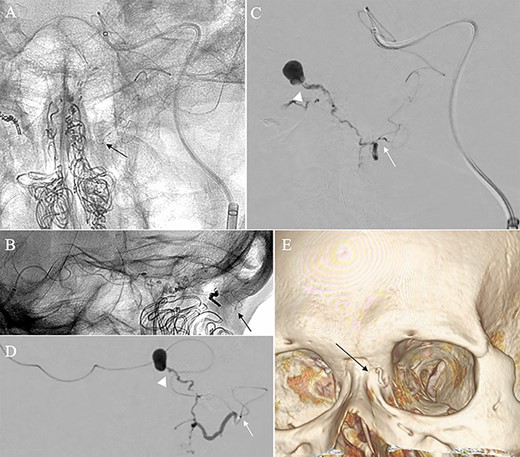

A patient in their 70s with extracranial lymphoma was incidentally found to have ACF–dAVF via head computed tomography and magnetic resonance angiography. Digital subtraction angiography (DSA) confirmed ACF–dAVF with multiple feeding branches, arising from bilateral OphAs, distal IMAs and the left middle meningeal artery (MMA), with cortical venous reflex (Borden type III, Cognard type IV) (Fig. 1). At the patient’s request, we chose endovascular, rather than surgical, treatment. We injected a 20% N-butyl-2-cyanoacrylate (NBCA)–lipiodol mixture into the fistula through bilateral ethmoidal arteries and the left MMA after we placed coils at the terminal branch of the right OphA. However, we could not achieve full penetration into the fistulous connections because of pressure secondary to high flow from the IMA branches, which resulted in incomplete obliteration (Fig. 1). Four months later, we repeated TAE by temporarily reducing nasal blood flow by inserting gauze infiltrated with xylocaine and epinephrine into the nasal cavities. After introducing the guiding catheter, an endonasal surgeon inserted X-ray-detectable surgical gauze infiltrated with 1% xylocaine and epinephrine (1:10 000) into bilateral nasal cavities using a nasal speculum, while paying full attention to avoid damage to the nasal mucosa. Then, we confirmed that the gauzes were placed in appropriate locations in the upper nasal cavity under fluoroscopic guidance. Immediately after insertion, we were able to confirm decreased blood flow from the IMA using DSA (Fig. 2). After this procedure, we navigated a DeFrictor Nano Catheter (Medico’s Hirata, Osaka, Japan) into the terminal branch of the OphA, which was connected to the dorsal nasal artery. Even though there was still a distance from the tip of the microcatheter to the shunt pouch, the NBCA reached the shunt point and penetrated the venous portion (Fig. 3). Follow-up DSA demonstrated complete obliteration of the ACF–dAVF, and blood flow in the nasal mucosa from the IMA branches recovered normally (Fig. 4).

Angiographic images, anteroposterior (A) and lateral (B) views, showing the microcatheter (arrow) navigated into the terminal branch of the left terminal branch of the ophthalmic artery, which connects to the dorsal nasal artery. Digital subtraction angiography, anteroposterior (C) and lateral (D) views, showing NBCA injected via the microcatheter (arrow) penetrating into the shunt point (arrowhead) without reflux of the NBCA. (E) Three-dimensional reconstruction of the skull showing the NBCA cast (arrow), which was embolized via the dorsal nasal artery.